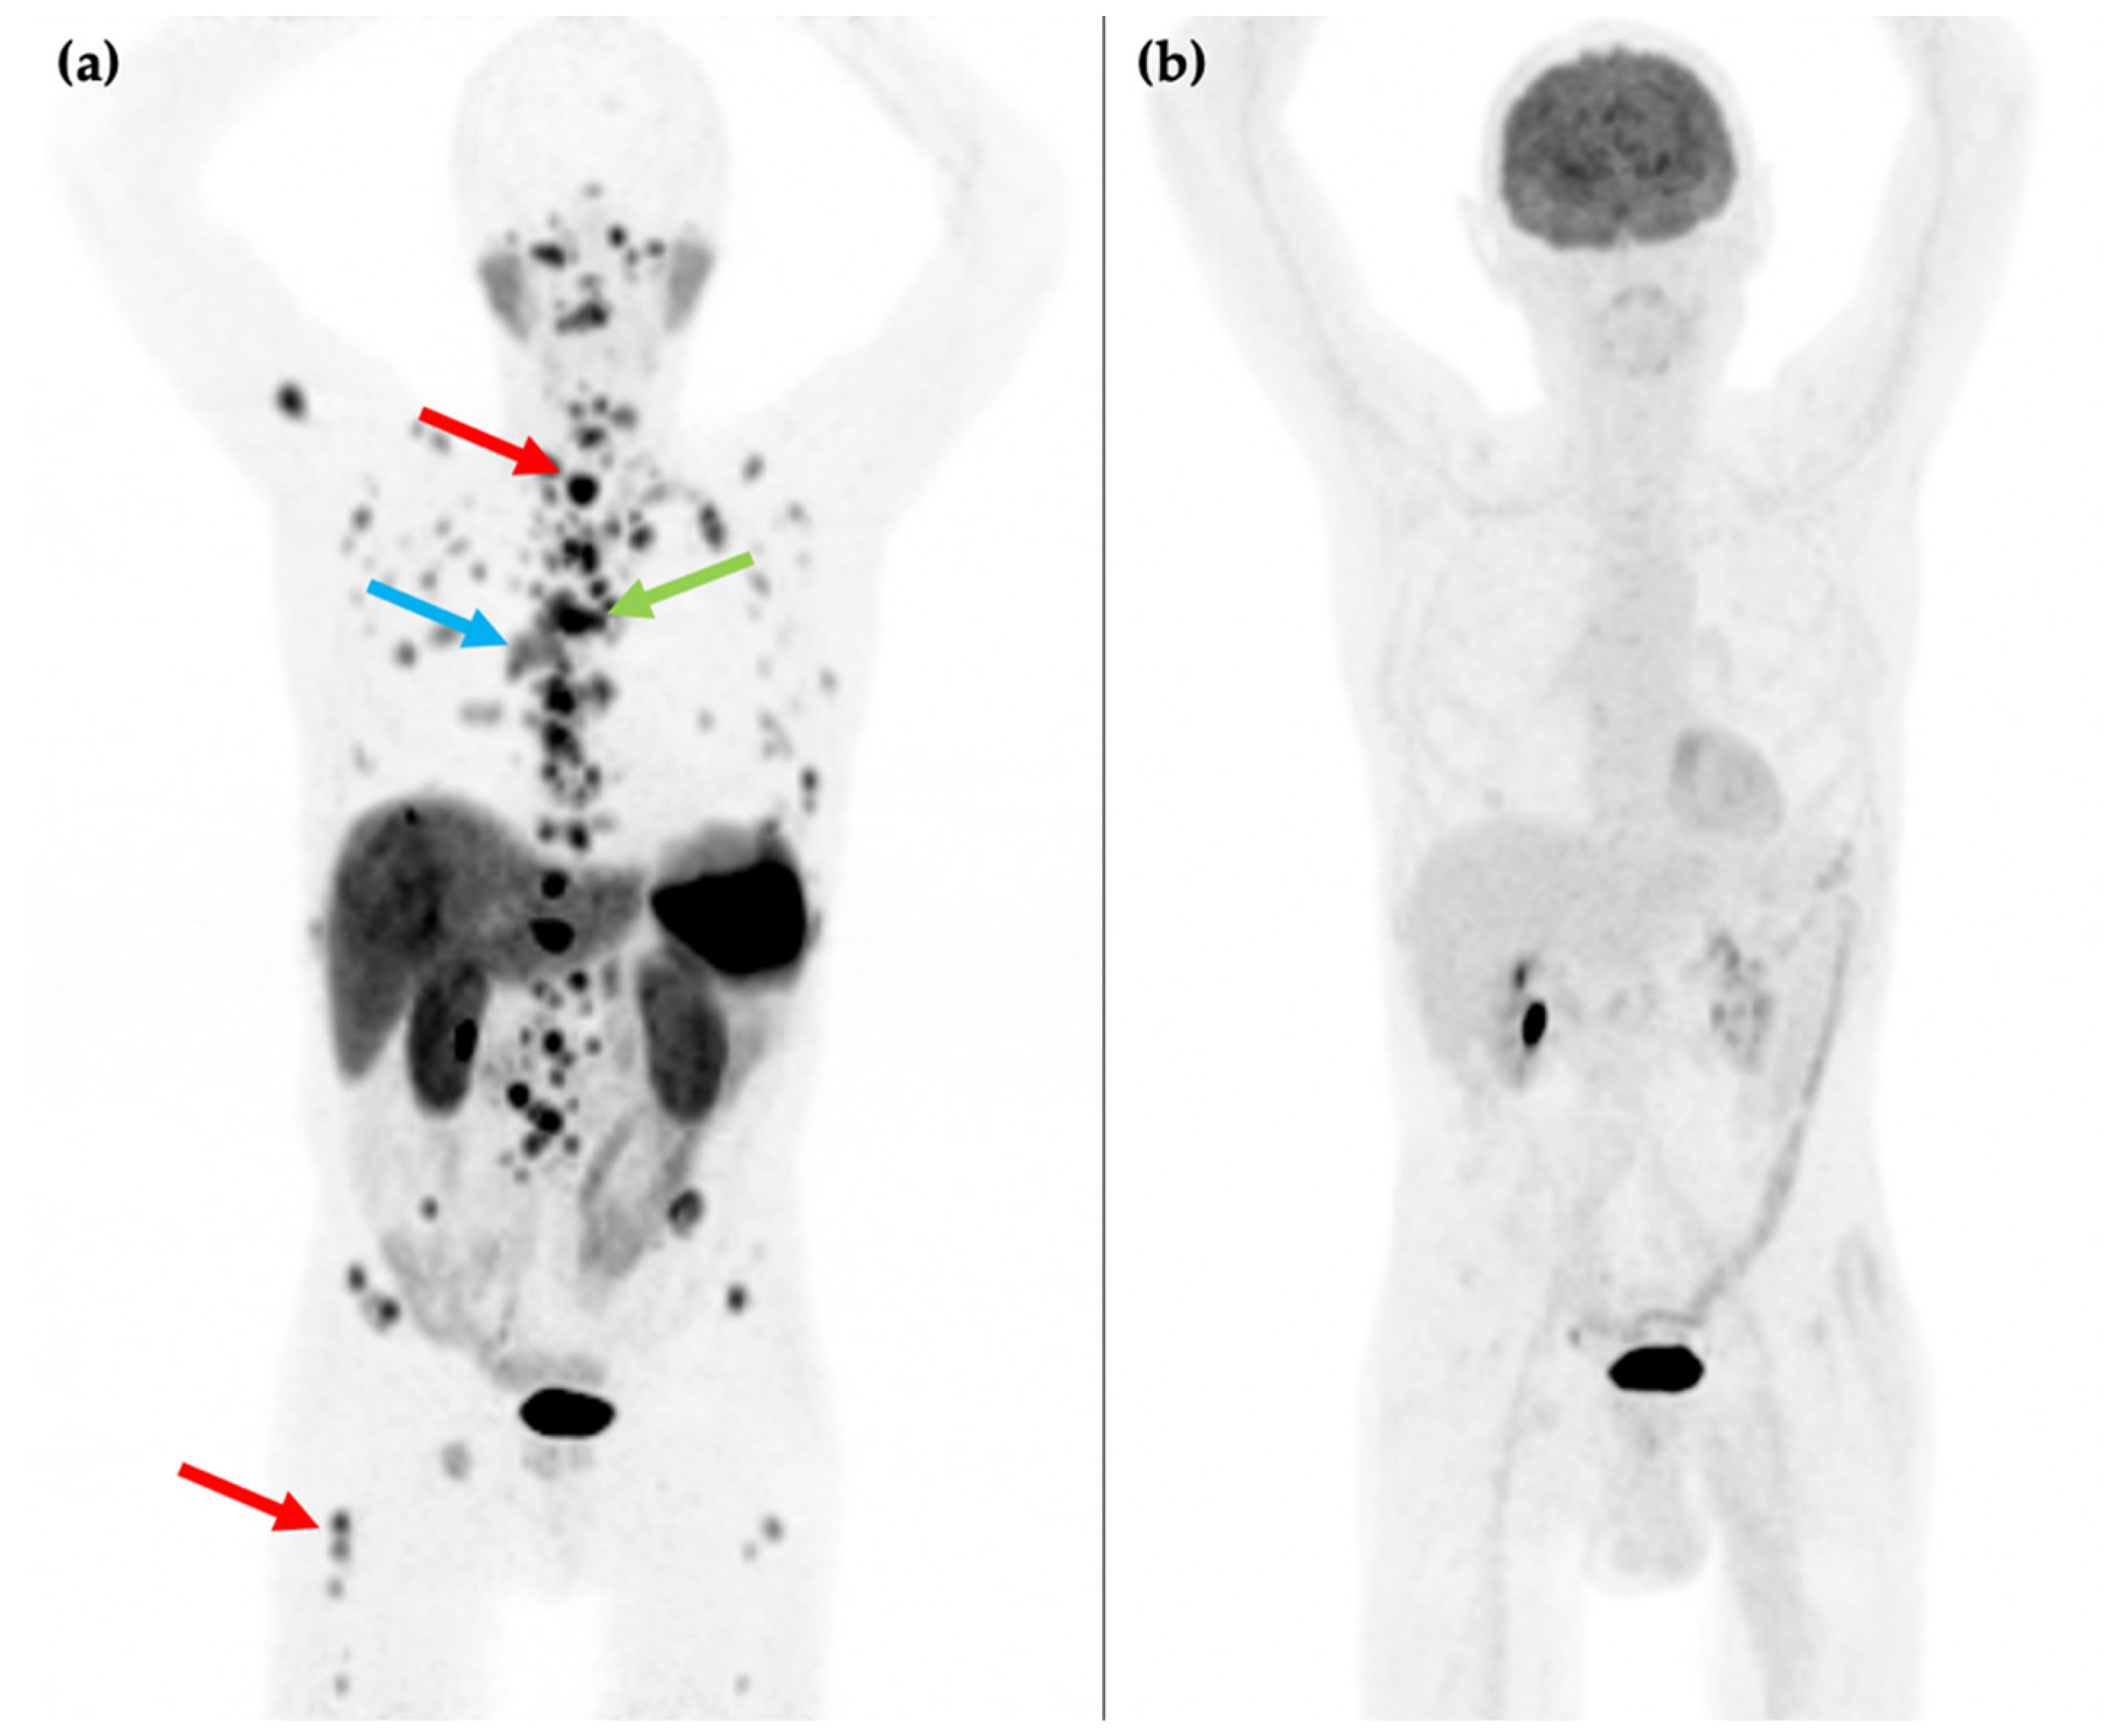

Figure 2.

81-year-old male with an endobronchial lesion identified on conventional CT imaging. 68Ga-DOTATATE PET/CT MIP image (a) shows an SSTR positive right-sided bronchial lesion (blue arrow), mediastinal lymphadenopathy (green arrow), and innumerable bone metastases in the axial and proximal appendicular skeleton including in the spine and right femur (red arrows). 18F-FDG PET/CT MIP image (b) shows that the SSTR positive lesions are not FDG avid. Histology confirmed a G1 typical bronchial carcinoid (Ki-67 1–2%).